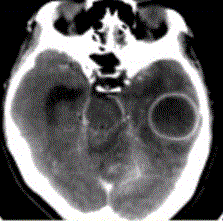

问题 患者女,26岁,头痛、低热10d余,既往有左侧慢性中耳炎病史。CT表现如下图。 脑脓肿的感染途径不包括

选项 A.中耳炎经鼓室盖直接蔓延 B.乳突炎直接蔓延 C.血栓性静脉炎所致 D.血行感染 E.淋巴途径感染

答案 E